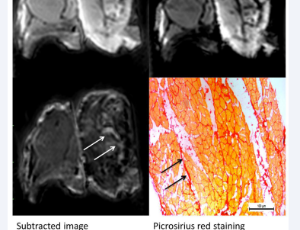

AbstractPurpose: Patients with cardiovascular disease often suffer from renal impairment.? We aimed to validate ultrashort echo time (UTE) T2* imaging without the use of any contrast agents in a phantom and patients with known cardiac fibrosis. Methods: A ph.....

AbstractPurpose: Here, we used dynamic T2 preparation pulse in weighted subtraction magnetic resonance imaging (MRI) among adult patients with coronary

artery disease (CAD) and children with congenital heart disease (CHD) to develop a new imaging method to.....